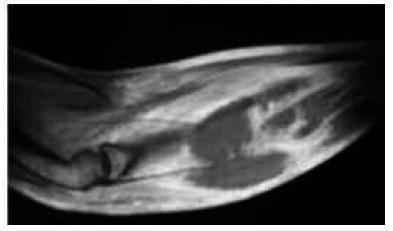

IMAGE CADAVERIQUE